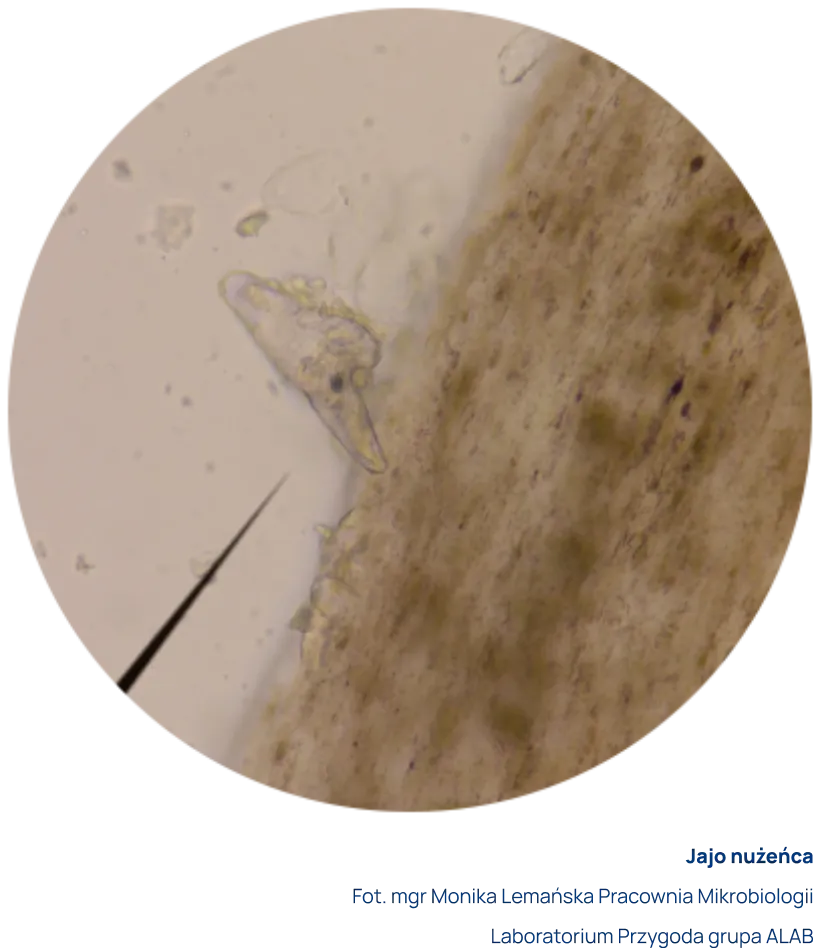

Za dodatni wynik uznaje się obecność w preparacie postaci dorosłych, larwalnych i/lub jaj nużeńca z jednoczesnym występowaniem objawów klinicznych